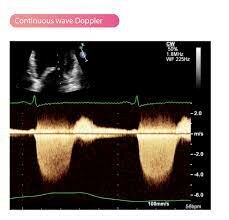

• Developments of the Wave Doppler

Developments of the Wave Doppler

Many developments including the continuous wave Doppler -aw many, spectral wave Doppler and color Doppler ultrasound instruments.